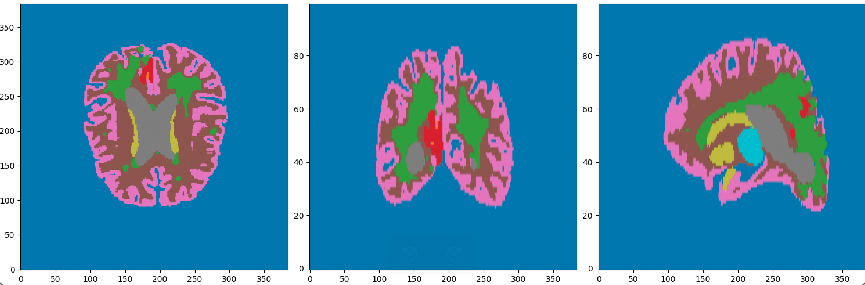

Régions

- WM (substance blanche)

- GM (Substance grise)

- Thalamus

- Ventricules

- Nécrose

- GDE (Rehaussement annulaire)

- Background

États

- Oedème

- Leucopathie

- autres Hyperintensité de T1ce

- Sain